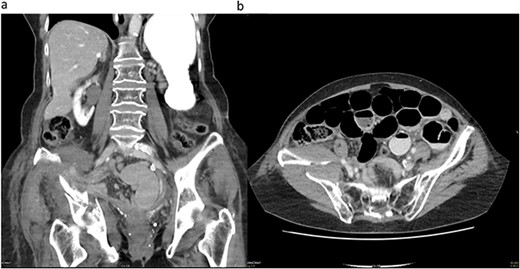

During hospitalization, the patient began vomiting, reported missing bowel movements and developed a distended abdomen with elevated bowel sounds. Blood tests indicated a decrease in haemoglobin to 117 (120–155 g/l) along with an elevated C-reactive protein (CRP) of 96.3 (<5 mg/l); lactate levels were not measured. A CT scan with intravenous contrast revealed a mechanical bowel obstruction with a distinct transition point from dilated to collapsed small bowel loops next to the fracture and a progressive haematoma. Radiologists initially misinterpreted the cause of the ileus, considering an increasing haematoma rather than herniated mesenteric fat with collapsed small bowel loops between parts of the acetabulum fracture as the potential cause (Fig. 1).

(a) Coronal CT image demonstrating the acetabulum fracture on the right side with herniated mesenteric fat tissue and collapsed small bowel loops (white arrow). (b) Transverse CT image demonstrating dilated small bowel loops and a distinct transition point (white arrow) on the right side close to the acetabulum fracture and a haematoma.